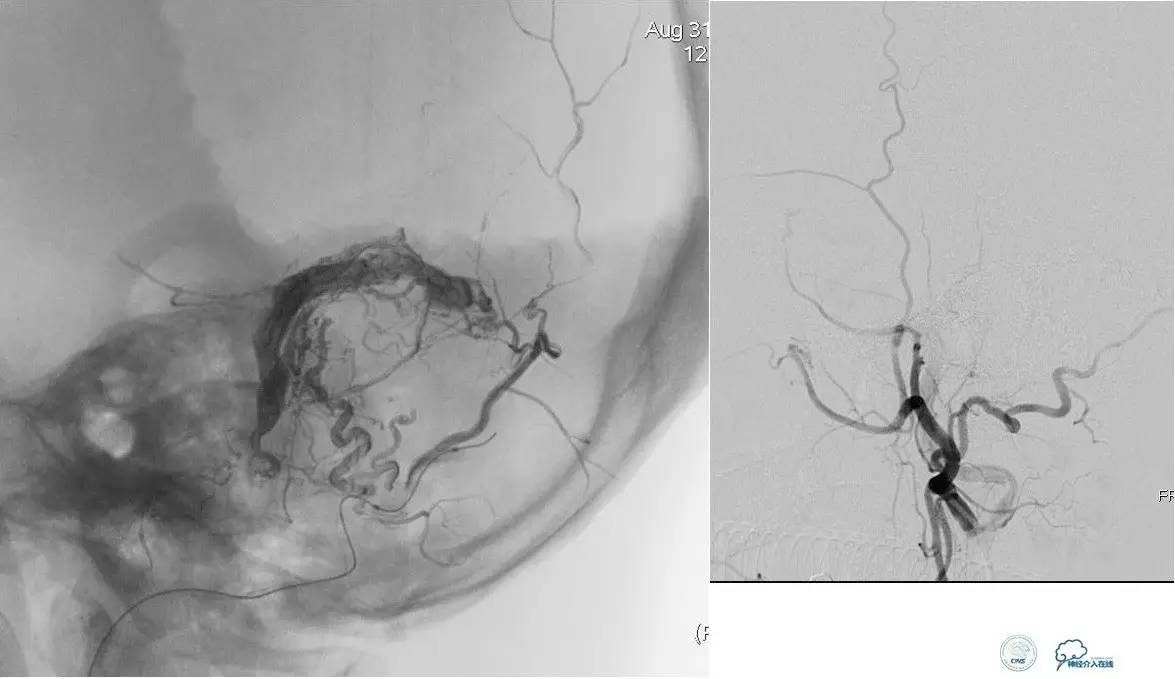

小脑幕缘区DAVF,只有颈外动脉参与供血,供血支细小。

选择抑制血管栓塞,胶无法弥散进入瘘口,选择另一支血管,近端防止Hyperform球囊。

最终胶弥散结果,瘘口完全消失。

小脑幕缘区DAVF,颈外动脉和颈内动脉的供血支均非常细小。

Marathon微导管进入分支后,在主干血管内放置Hyperform球囊。

最终的栓塞结果。